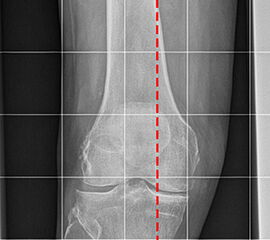

Aufnahmen zur Bestimmung der Bein- und Rückfussachse

Einbeinstandaufnahme

Indikation:

• Beurteilung der Beinachse. Aufnahme zur Planung einer endoprothetischen Versorgung oder zur Planung von Achskorrekturen.

Positionierung:

• Der Patient steht auf beiden Füßen mit gleichmäßiger Lastverteilung.

• Die Kassette befindet sich dorsal des Beins und steht senkrecht zum Boden.

• Die Fußlängsachse verläuft nach ventral.

• Um Verzerrungen zu reduzieren wird die Aufnahme in 3 Teilaufnahmen angefertigt und die Bilder danach digital zusammengefügt.

• Die erste Aufnahme umfasst die Region vom Beckenkamm bis proximales Drittel des Femurs. Der Zentralstrahl ist auf das Hüftgelenk zentriert.

• Die zweite Aufnahme umfasst die distalen zwei Drittel des Femurs und das proximale Viertel der Tibia. Der Zentralstrahl ist auf das Kniegelenk zentriert.

• Die dritte Aufnahme umfasst die distalen Dreiviertel der Tibia mit Fuß und Sprunggelenk. Der Zentralstrahl ist wird mittig auf das Sprunggelenk zentriert.

• Die Röntgenröhre steht bei allen drei Aufnahmen 0° horizontal

Kennzeichen des Röntgenbildes:

• Abbildung des gesamten Beins.

• Die Aufnahme ist Basis aller Achskorrekturen.

• Zur Bestimmung der Beinachse wird die Mikulicz-Linie eingezeichnet. Sie verläuft vom Hüftkopfmittelpunkt zur Mitte der Talusrolle.

• Bei einer physiologischen Beinachse verläuft diese Linie durch die Mitte des Kniegelenkes (Eminentia intercondylaris des Tibiaplateaus). Beim Genu varum (O-Bein) verläuft die Mikulicz-Linie medial der Eminentia interconylaris, beim Genu valgum (X-Bein) lateral der der Eminentia interconylaris.

Besondere Bemerkungen zum Beispielbild:

• Valgusarthrose des Sprunggelenks.

• Diskret varische Beinachse bei medial betonter Arthrose des Kniegelenks.

• Lateral des OSG ist eine Eichkugel eingeblendet, die als Referenz bei der Planung von Endoprothesen dient.

• Verkalkung medial in den Weichteilen des Unterschenkels.